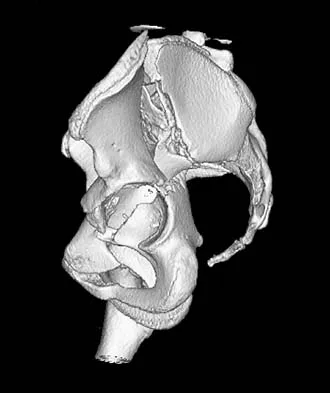

What is the best surgical approach for the scapular fracture shown in Figure 46?

Explanation